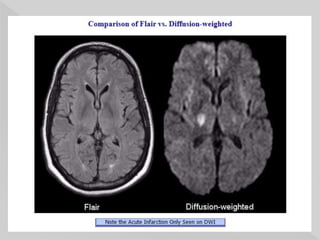

 a special inversion recovery sequence with a

long inversion time.

 This removes signal from the cerebrospinal

fluid in the resulting images.

 similar to T2 weighted images with grey

matter brighter than white matter but CSF is

dark instead of bright.

 The FLAIR sequence is part of almost

all protocols for imaging the brain, particularly

useful in the detection of subtle changes at the

periphery of the hemispheres and in the

periventricular region close to CSF.

 The usefulness of FLAIR sequences in many

diseases of the central nervous system:

 infarction

 multiple sclerosis

 subarachnoid hemorrhage

 head injuries, and others.

 Post-contrast FLAIR images - to assess

leptomeningeal diseases, such as meningitis

Fat – bright

White matter –

Dark

Gray matter -

White

CSF – Dark

FLAIR

SEQUENCE